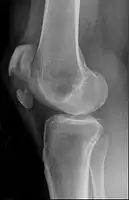

Transverse fracture of patella